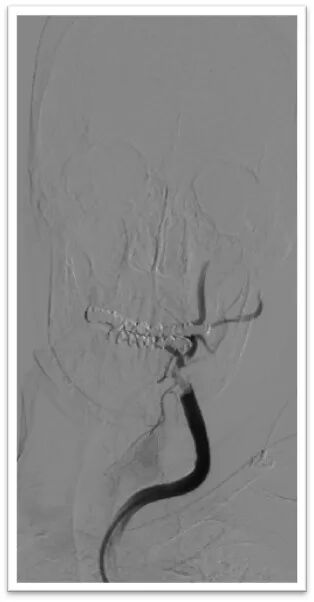

Synchro2微导丝引导微导管通过闭塞段后造影位于血管真腔,交换长导丝Synchro 300mm,顺利置入保护伞Spider 4mm于岩骨段,微导管释放6-30mm支架后造影显示支架完全覆盖血栓,正向血流未完全恢复,停留5分钟后在支架锚定下前推长鞘,使用抽拉结合取栓术取出大量血栓;

微导丝引导微导管顺利置于左侧大脑中动脉上干,半释放6-30mm支架,停留5分钟后完全取出血栓,造影显示左侧大脑中动脉血流完全恢复,mTICI:3级。